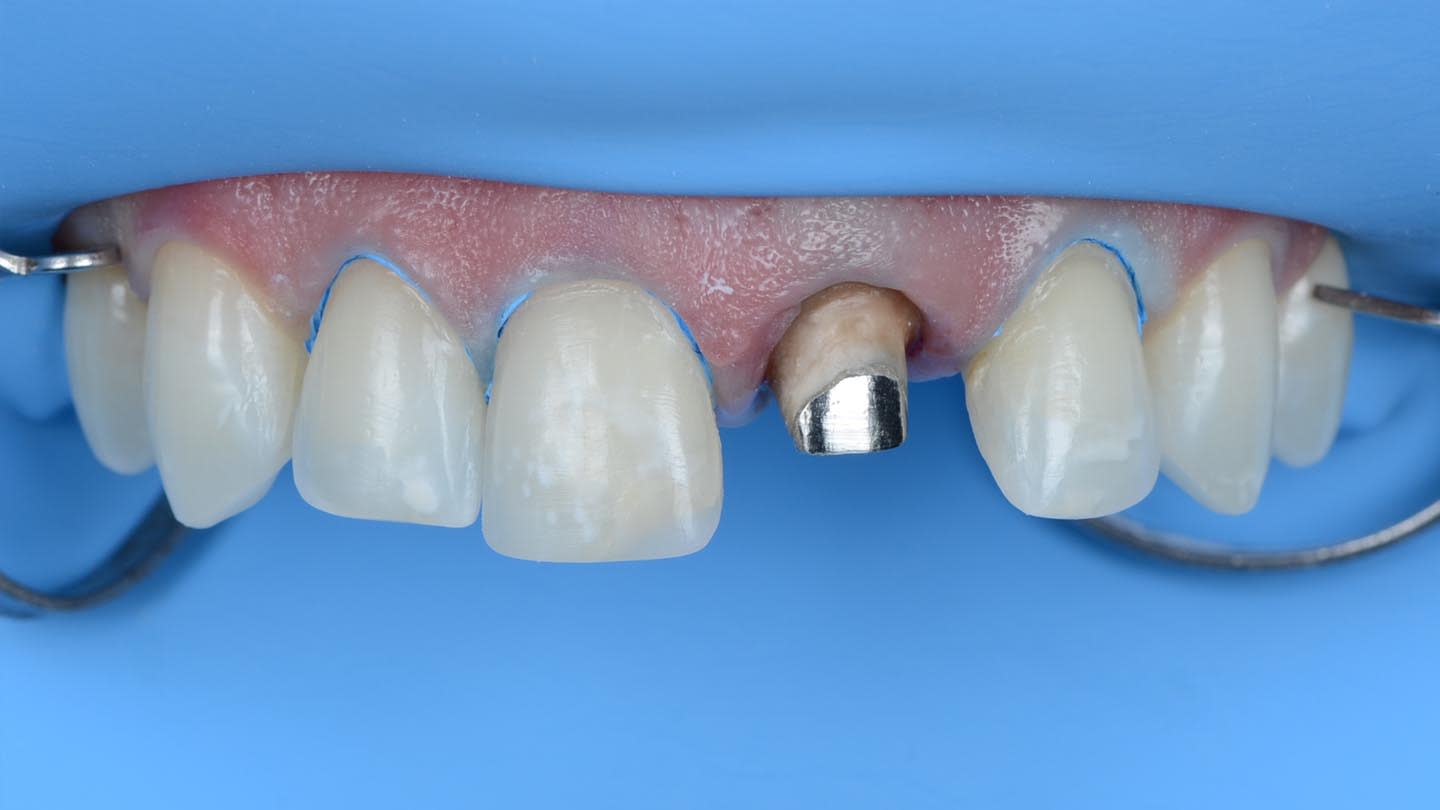

The opaque-core crown was tried-in on tooth No. 9 and approved in terms of marginal fit, preparation adaptation, and shade matching with the adjacent incisors. After this assessment, the crown was prepared, similar to the remaining teeth, to receive a ceramic veneer. A new digital intraoral final impression (TRIOS 4) was made for all four maxillary incisors, and the standard tessellation language (STL) files were sent to the laboratory for the manufacture of lithium-disilicate porcelain veneers (IPS e.max) using subtractive milling technology (PrograMill® PM5, Ivoclar). All data transfer from 3D planning to the laboratory CAD/CAM process is faster, easier, and more predictable than conventional methods, resulting in less manufacturing time and chairtime and enhanced final esthetic results (Figure 7 and Figure 8).16-18

Rubber dam was used when bonding the final restorations. The veneer corresponding to tooth No. 9 was initially bonded to the opaque-core crown extraorally following standard protocol for silica-based ceramics,19 which included 9% hydrofluoric acid-etching (Porcelain Etch, Ultradent, ultradent.com), silane application (Monobond Plus®, Ivoclar), and application of a light-curing resin cement (Variolink® Esthetic LC, neutral shade, Ivoclar) (Figure 9 through Figure 13).